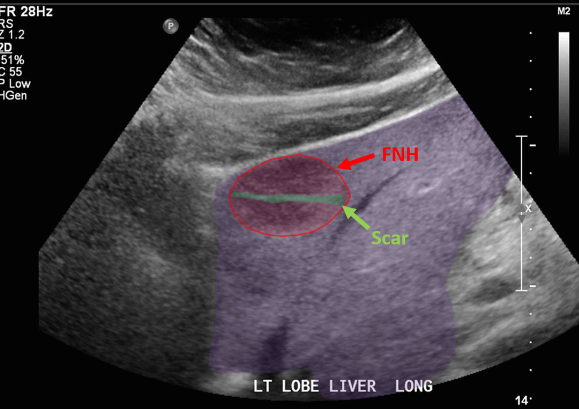

FNH (Focal Nodular hyperplasia) US finding

- isoechoic lesion

- central feeding artery

위에서 보인 초음파소견처럼 FNH는 경계가 명확한 균일한 종괴이며 내부에 섬유성 반흔이 있다. 에코는 저에코를 갖지만 간혹 고에코나 등에코등 다양하게 나타날 수 있으며 피막이 없다. 도플러상 과혈관성을 보이며 정상 간세포조직을 갖는다. 초음파 만으로 간암과 구별할 수 없으므로 혈액검사, CT 와같이 다양한 검사를 통한 진단이 필요하다.